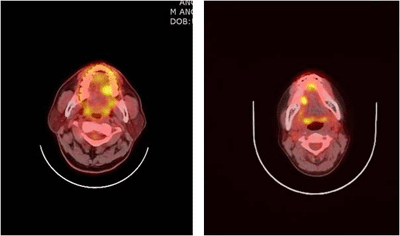

양전자방출단층촬영(PET)는 각 장기의 생화학적, 생리적 반응을 정량화하여 진단, 치료방침설정 등에 활용하는 영상기법으로 양전자의 방출 후 나타나는 광자를 검출기를 통해 검출하는 것을 기본원리로 합니다. 구강점막 등에 발생한 악성흑색종에 대한 병기 결정에도 도움이 되는 것으로 알려져 있습니다.

[ 좌측, 우측 설암의 양전자방출단층 촬영 이미지 ]